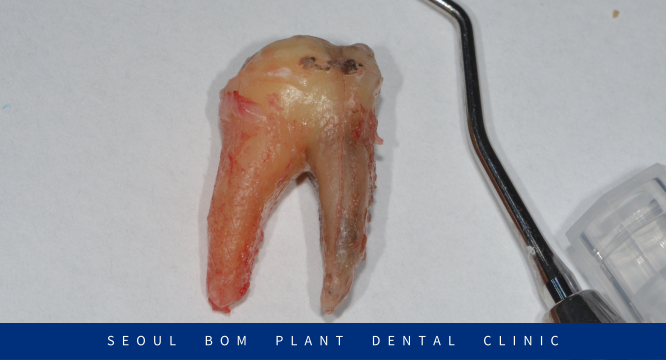

아래턱 왼쪽 첫 번째

어금니(#36)를 발치한 후

주변 염증조직을 꼼꼼하게 제거한 뒤

깨끗하게 소독을 진행했습니다.

발치한 치아를 확인한 결과

뿌리 중에서 앞쪽에 있는 뿌리가

길게 세로로 치아머리부터 뿌리까지

파절이 일어나 까맣게 되어 있는 것을

확인할 수 있었습니다.

보이지 않는 곳에서

수직 치근 파절이 일어나면서

염증이 진행되었던 것인데요.

염증이 심했던 치아라 발치 후

주변 잇몸뼈가 차고 아물었을 때

임플란트 식립을 하기로 했어요.